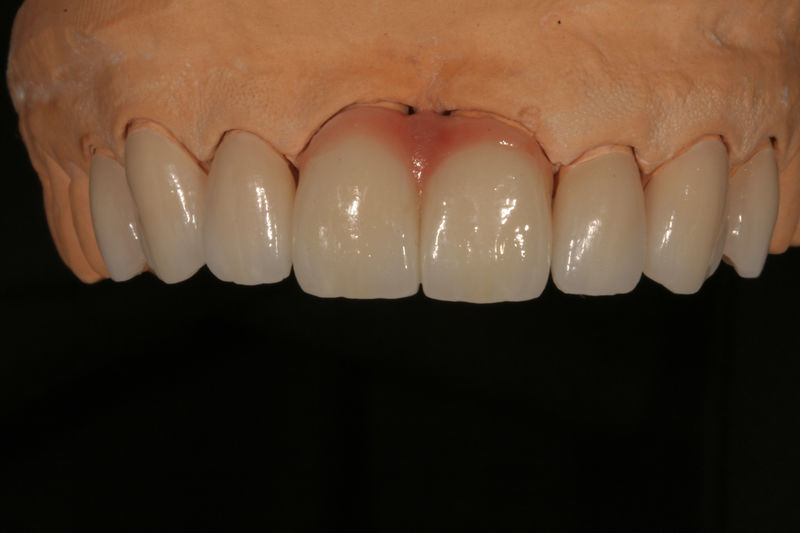

Son restauraciones que cubren toda la cara frontal del diente, generalmente empleadas en el sector anterior y cuya finalidad es primariamente estética.

Restauraciones fabricadas en el laboratorio con materiales estéticos, los cuales cubren de manera total dientes anteriores y posteriores. Se utilizan primariamente para restaurar dientes con caries, fracturas y/o defectos amplios, así como soportes de puentes. Para poder enviar el caso al laboratorio se toman impresiones utilizando materiales de impresión o técnicas modernas digitales.